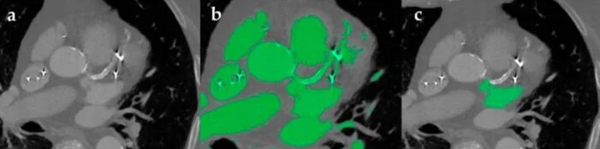

對(duì)心臟圖像進(jìn)行分割的過(guò)程,其中會(huì)包含由金屬植入物和動(dòng)脈鈣化造成的明亮偽影。b部分顯示了自動(dòng)分割,但由于人工制品的存在,該分割的效果有所減弱。B部分展示了如何使用手動(dòng)分割來(lái)隔離感興趣的區(qū)域。(照片來(lái)源:Segaran等人)